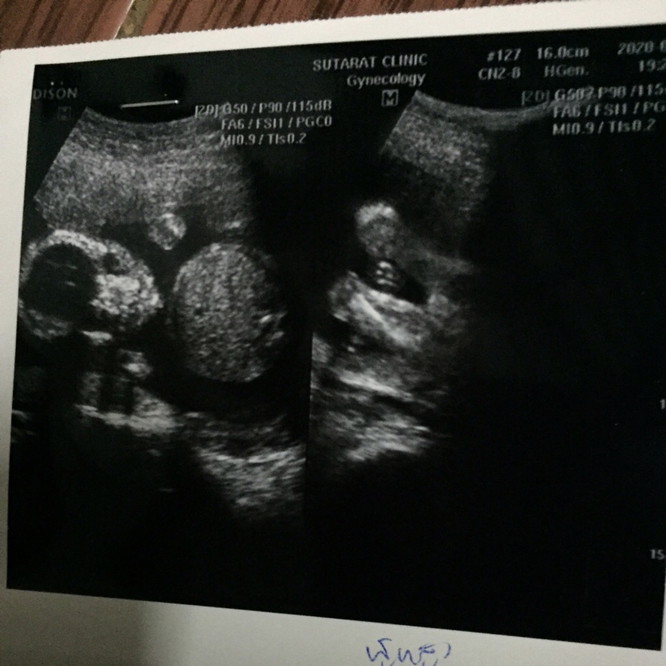

แบบนี้เพศหญิง หรือเพศชายคะ

ชายค่ะ ในใบซาวด์บอกเพศชัดเจนเลยค่ะแม่🥰

ใบซาวด์บอกเพศอยู่นะคะ male เพศชายค่ะแม่

ในใบซาวด์ระบุเพศว่าเป็นชายค่ะแม่

ใบซาวน์นี้เป็นส่วนก้นน้องค่ะแม่ ตอนนี้7เดือนแล้วค่ะ

ชายค่ะ จู๋น้องนำหน้ามาเลยค่ะ55